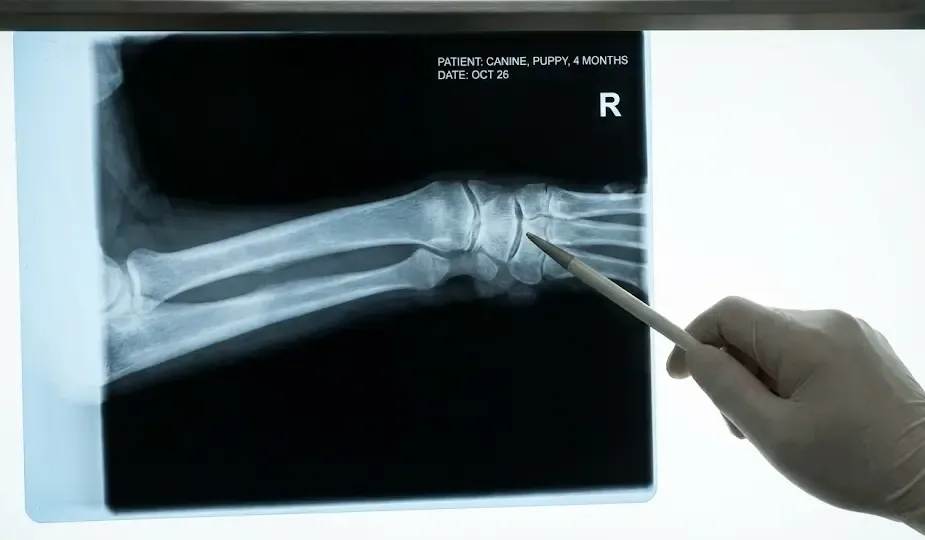

8. Señales de Alerta en el Crecimiento

Vigila a tu cachorro mientras camina. Si notas algo de esto, acude al veterinario:

- Cojeras intermitentes: Hoy cojea de una pata, mañana de otra.

- Patas en “X”: Los corvejones se juntan y las patas traseras se ven desviadas.

- Dificultad para levantarse: Especialmente después de dormir (parecido a los síntomas en perros senior).

- Causas calcificación prematura: Los cartílagos de crecimiento se cierran antes de tiempo o el hueso crece con picos e irregularidades (osteocondrosis).

Cuidado: Un crecimiento demasiado rápido es el enemigo número uno de las articulaciones. Si el músculo y la grasa aumentan de peso más rápido de lo que el hueso puede endurecerse, el esqueleto se “dobla” bajo la carga. Esto es especialmente crítico en los primeros 6 meses de vida.